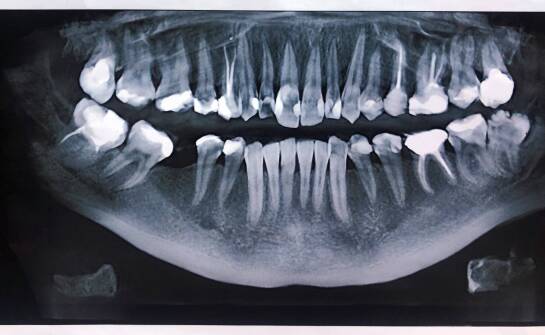

Jak RTG zębowe wspiera planowanie zabiegu podniesienia dna zatoki szczękowej?

RTG zębowe jest podstawowym narzędziem w diagnostyce stomatologicznej. Pozwala na uzyskanie szczegółowego obrazu struktur zębowych, kości szczęki oraz okolicznych tkanek. Dzięki temu lekarze mogą obserwować zmiany anatomiczne i wykrywać nieprawidłowości, które nie są widoczne gołym okiem podczas rut